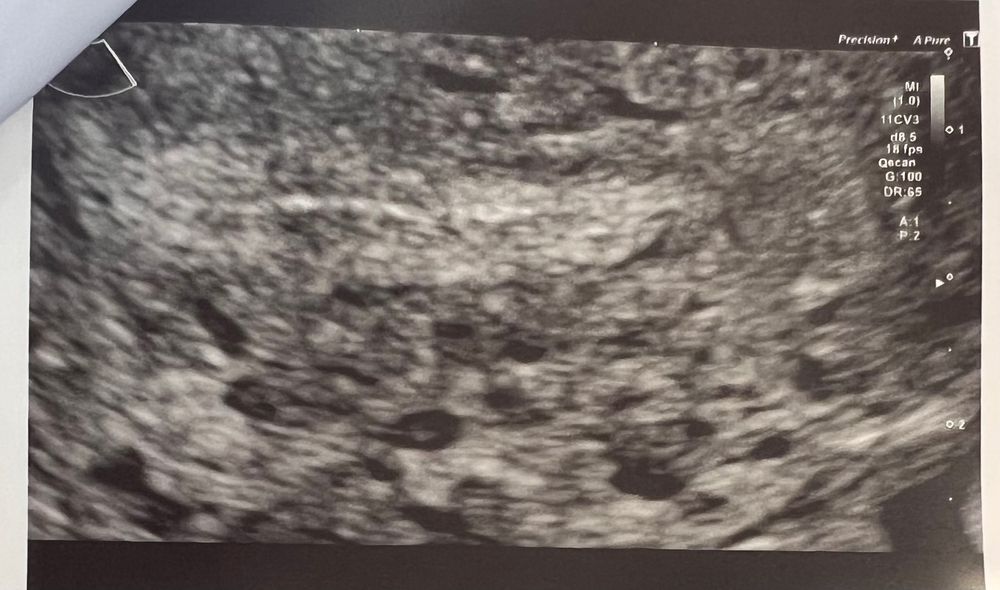

Эндометрия плоха растет

Эндометрия плоха растет 112 фотографий